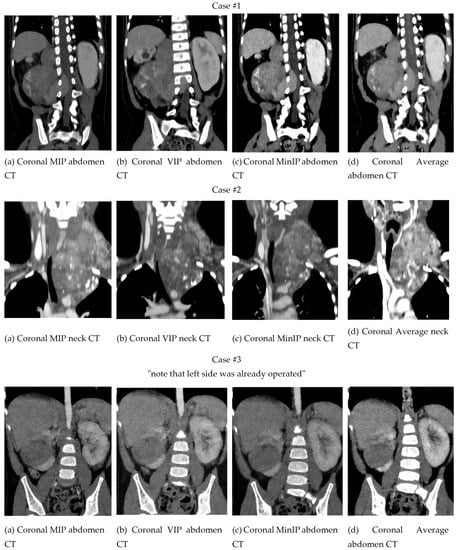

3.1.1. Two-Dimensional Projection Renderings

2.4.1. Multiplanar Reconstruction

2.4.2. Maximal Intensity Projection

2.4.3. Volume Rendering